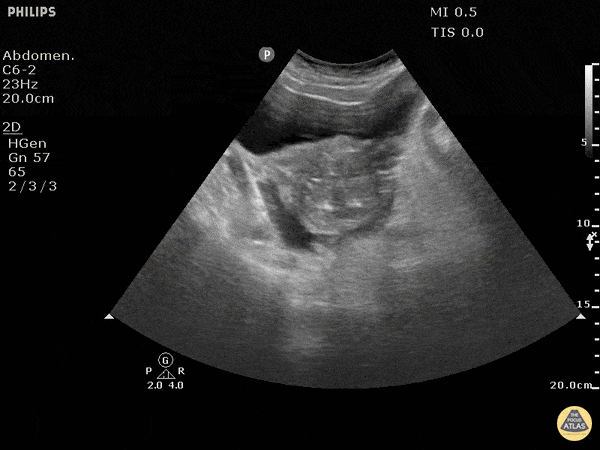

Trauma - Positive FAST Pelvis - Transverse

Blunt trauma patient with POSITIVE FAST scan. The uterus can been seen floating in free fluid. Dr. Justin Bowra